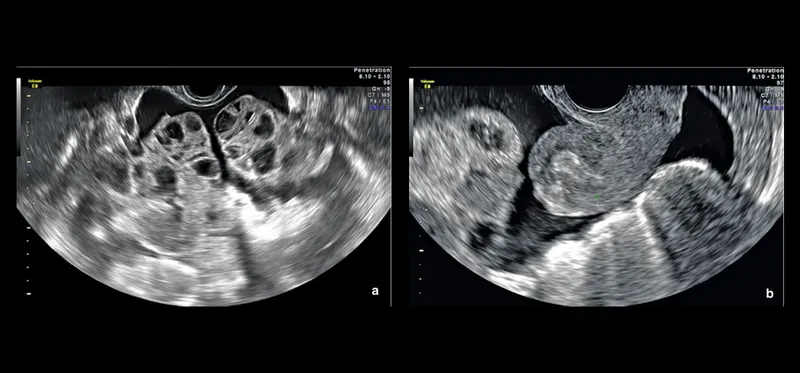

- Transvaginal Ultrasound (TVS): Antral Follicle Count (AFC), uterine/adnexal pathology

- Transvaginal Sonography (TVS): Follicular growth (serial), endometrial thickness (target ≥7-8 mm).

- ⚠️ Risks: PCOS, young, high AMH/AFC, E2 >3500 pg/mL.

- Features: Ovarian enlargement, ascites, hemoconcentration (Hct >45%).